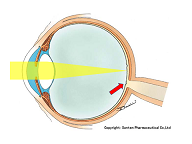

黒目(角膜)から入ってきた光は、目の奥の方のフィルム(網膜)に当たります。網膜は一つの束(視神経)になって、最終的には脳ミソにつながり、「物が見える」という事になります。

図の赤矢印の部分は視神経乳頭と言って、網膜が集まって束になる部分なのですが、実はこの部位のみ光を感じ取ることはできないのです。